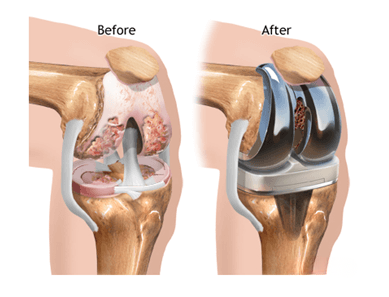

Knee replacement surgery, also known as Total Knee Arthroplasty, involves replacing the damaged cartilage and bone surfaces of the knee joint with smooth, durable artificial components.

Modern knee implants are designed to closely mimic natural knee movement and are highly durable.